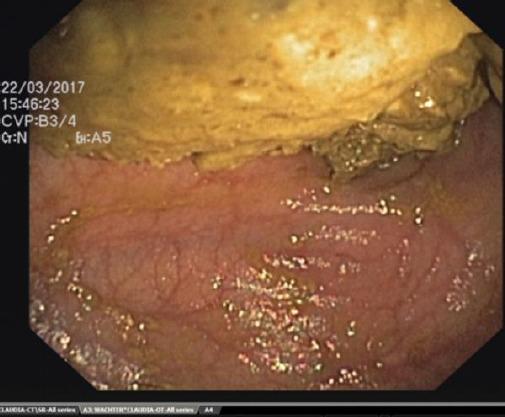

Caecum volvulus (CV) is defined as an axial twisting that causes an inversion position of the caecum, ascending colon and terminal ileum. This anatomical finding is responsible for some clinical features. Obstruction and strangulation are the most important and life-threatening.

We are presenting a 50 years old woman presented to the hospital with sudden acute severe abdominal pain and distension of about 24 hours associated with vomiting and no flatus.

盲肠扭转(CV)被定义为一种导致盲肠、升结肠和回肠末端发生倒转位置的轴向扭转。这一解剖学发现导致了一些临床特征。梗阻和绞窄是最重要且危及生命的。

我们报告一名50岁女性,因突发急性剧烈腹痛和腹胀约24小时入院,伴有呕吐且无排气。